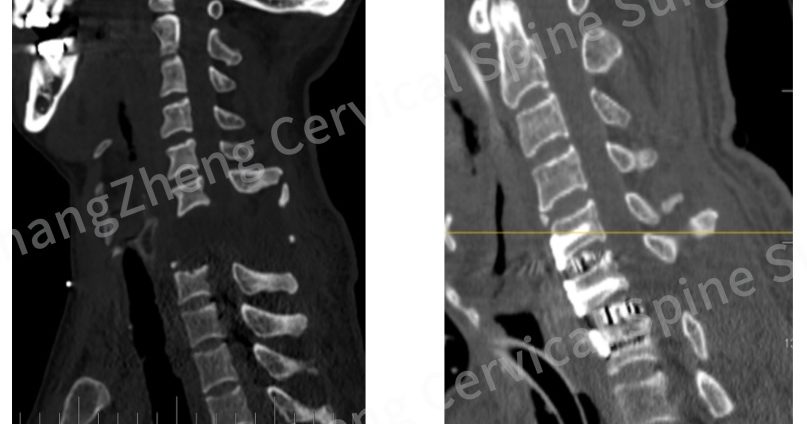

中国医院奇迹救回“颈椎断开”患者 医生:情况恶劣如断头